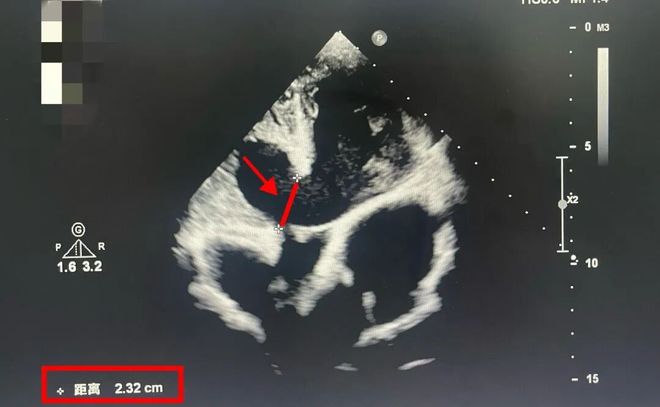

彼时,14岁的李小并不知道,他的心脏缺口已经“裂”开长达22毫米。 什么概念?室间隔缺口>5毫米,就一定要动手术“维修”了。 而李小心脏的这个裂口,已经超过正常手术指征的4倍。他的心脏射血分数已经低于50%(正常是50%-70%)。 这意味着,李小心脏的泵血战斗力,一直在走“下坡路”。再拖下去,就是心衰。能活到几岁?没人敢讲。

红色线段标注出来的那一小截,就是李小的室间隔缺损缺口 换句话说,长大,对他来说,可能是一件很“遥远”的事。 2025年5月份,清远市委统战部和顺丰公益基金会顺丰暖心项目团队、港大深圳医院,在当地办了一个义诊。而李小命运的齿轮,也从此刻开始转动了。香港大学深圳医院儿童心脏外科主任丁以群团队筛查出6个需要手术的先心病孩子。李小,是其中一个,也是病情最重的一个。